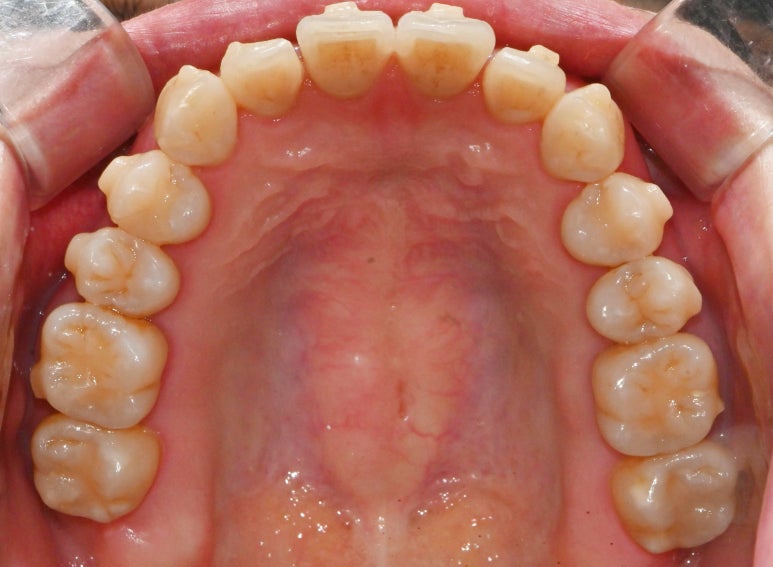

서울대입구역 교정 치과 를

처음 찾아오셨을 당시

구강을 살펴보면

윗니들이 삐뚤빼뚤한 것이 관찰됩니다.

우리는 이것을 총생(crowding)이라

부르며,

두 개의 앞니도 정중선이 맞지 않고

한쪽으로 쏠려있어 보이네요.

또한 사진에서는 잘 보이지 않으나

맨 뒤에는 사랑니도 남아있었습니다.